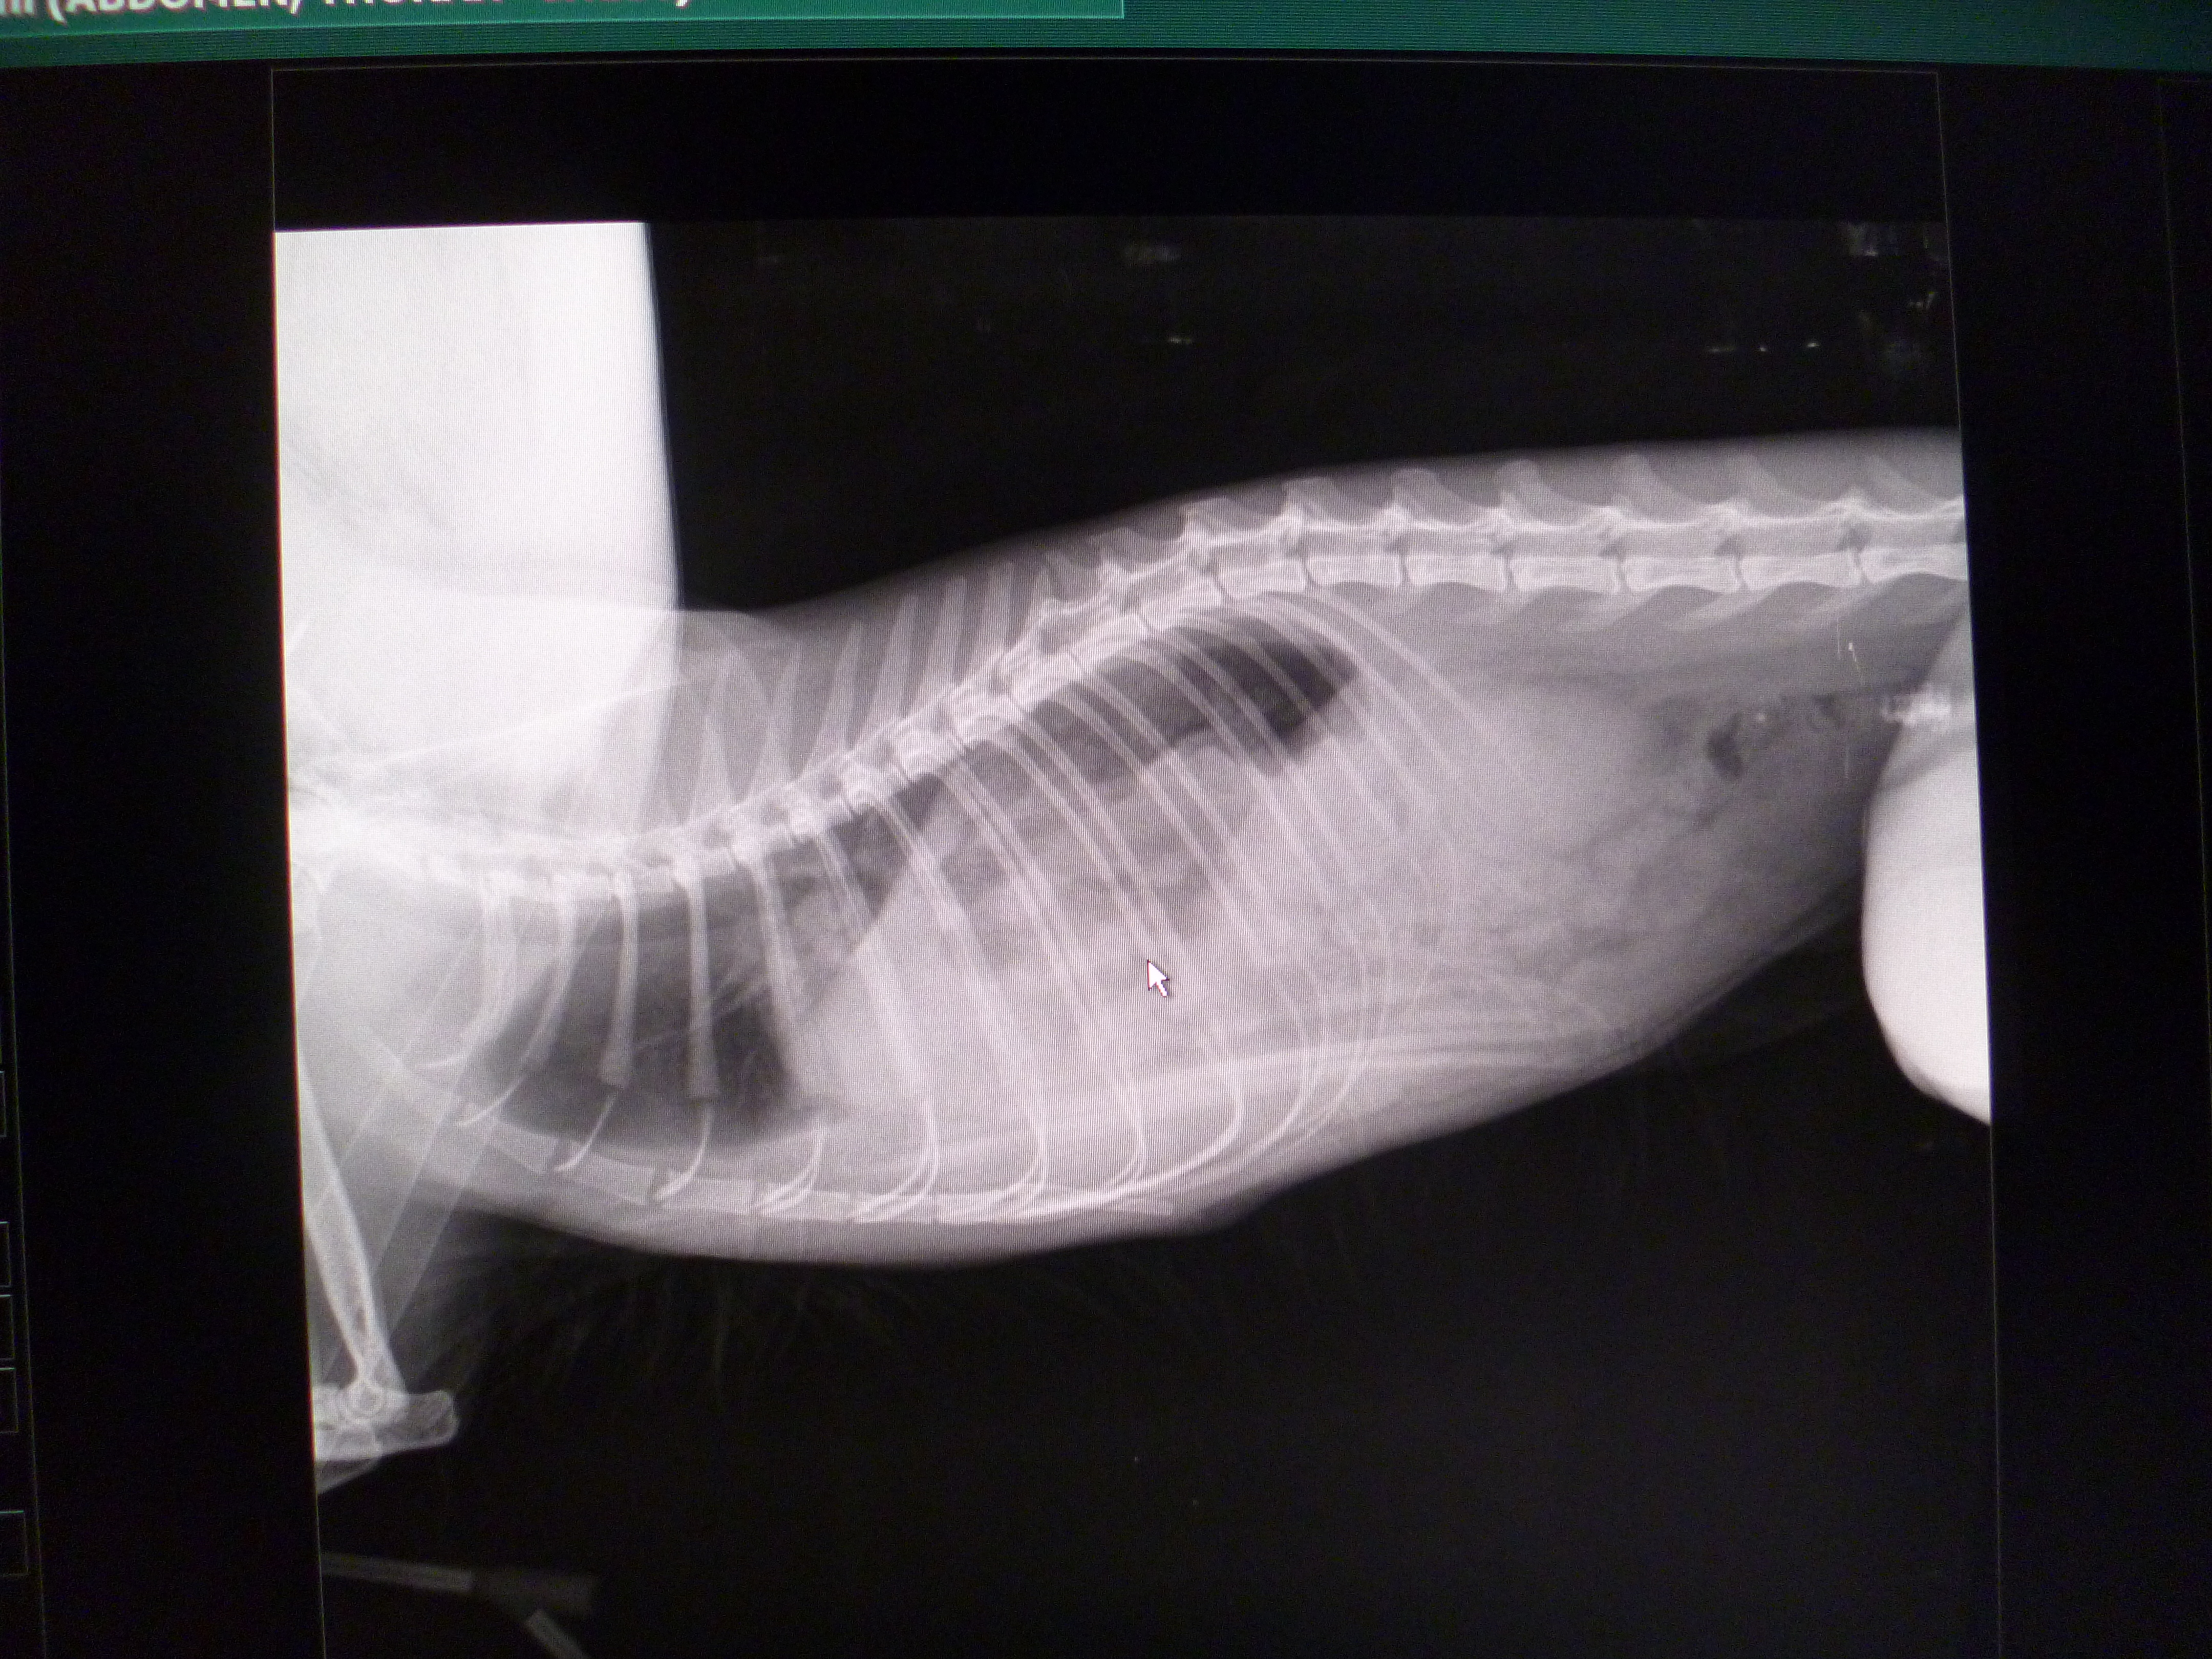

Minnie came in as an emergency and during the clinical exam it was quite clear that her respiratory rate was increased and it was taking a lot of effort for her to draw in each breath. She was also very dehydrated from being missing and was covered in tiny maggots. I admitted her and she was cleaned and rehydrated with intravenous fluids. The next day she was a little more stable and we were able to x-ray her so we took x-rays of her whole body as we had no idea what had happened while she was missing.

The x-rays showed she was suffering from a ruptured diaphragm and the hole was allowing abdominal organs into her chest cavity which was causing the breathing difficulties. These sort of injuries are common secondary to blunt trauma such as in a road traffic accident. She was taken to surgery and we pulled her stomach, liver and intestines gently back into her abdominal cavity before suturing the hole in her diaphragm.

Cursor shows approx. furthest extent abdominal organs should extend to.